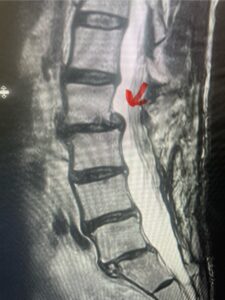

In this next case, this patient is a 47 year-old female who presents with intractable low back pain with severe pain, numbness, and weakness in the right lower extremity that had gotten progressively worse over a year. The patient had failed conservative management including physical therapy and epidurals. She was noted to have ⅘ weakness of plantar flexion. MRI demonstrated a large right L5-S1 disc herniation with severe compression of the descending right S1 nerve root (Fig 3). It was decided to perform a right L5-S1 hemilaminectomy for removal of the disc fragment and decompress the S1 nerve root. When you expose the disc, one must be certain to release any anterior adhesions to the nerve root in order to prevent a dural tear during retraction of the nerve root. It is also important to make sure during exposure and you finally encounter the dura after removing the ligamentum and fat, to make sure you are looking at the nerve root and not the main trunk of the thecal sac because if you don’t you can avulse or damage the nerve root if you retract the wrong structure.

Fig. 3a: Sagittal and axial T2-weighted lumbar MRI images demonstrating large right L5-S1 disc herniation (red arrows)